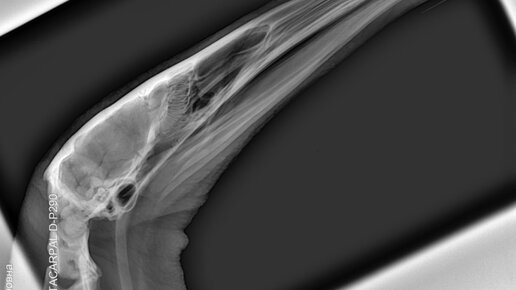

«Легче предупредить, чем лечить» - говорил знаменитый Гиппократ. Этому правилу до сих пор следуют не только обычные «человеческие» врачи, но и их «зверские» коллеги - ветеринары. Проще всего предупредить болезнь, когда пациент проходить регулярный осмотр, то есть – диспансеризацию. Вот только, если человеку для этого надо пройти семь, а то и восемь кругов поликлинического ада, животным никуда ходить не требуется: ветеринарный врач придет к ним сам, а если надо, и коллег с оборудованием приведет. Диспансеризацию, как ремонт, закончить нельзя...